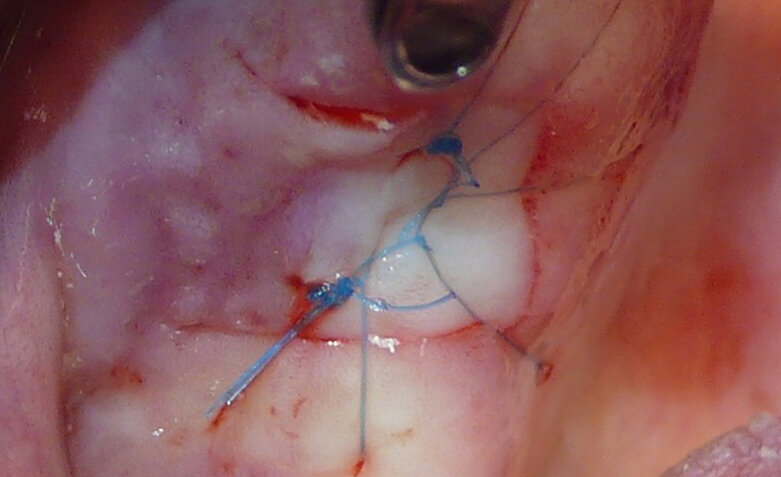

Figure 1 shows a split-mouth case with a bilateral INTRALIFT procedure: after a small crestal “booklet”-flap of approx. 7x7mm is detached, the sinus floor is safely opened with ultrasound Piezotome tips (Figs. 2 & 3), the sinus membrane then detached by the hydrodynamic cavitation effect of the Piezotome-tip TKW5 plugged into the approach canal (Figs. 4 & 5) and the subantral scaffold filled with 2cm of randomly assigned biomaterial (Figs. 6 & 7), followed by wound closure (Fig. 8). After a mean healing period of 8,4 months X-Mind trium CBCT scans were performed, the digital setup of the future bridge constructed with the AIS 3D app and the bone density determined in the sinus-lift site around a virtual implant (Fig. 9). Standardised implants (4mm in diameter and 12mm in length) were then inserted in the position of the virtual implant and insertion torque values (ITV) measured intra-surgically (test groups; Fig. 10). A total of 27 patients with sufficient native subantral crestal bone (min. crest width: 6 mm, height: 12 mm) were screened by X-Mind trium CBCT for bone density with the virtual implant (Fig. 11), the standardised implant inserted and the ITV recorded (control group). Figure 12 depicts the final result after implant insertion in the patient case shown in Figures 1–9.